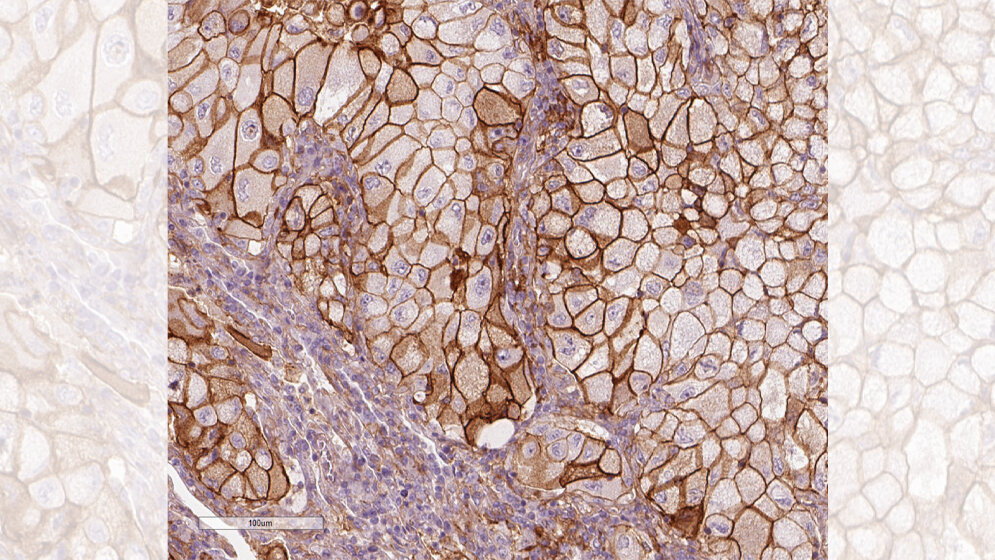

Den Einfluss von PD-L1 auf die Prognose bei Lungenkrebs hat Dr. Karolina Edlund vom Leibniz-Institut für Arbeitsforschung an der TU Dortmund (IfADo) erforscht. Bei Krebs kommen verschiedene Therapien zum Einsatz. Von besonderem Interesse ist die Krebsimmuntherapie, bei welcher von Krebszellen zunächst gehemmte Immunzellen wieder aktiviert werden. Für die Aufklärung der zugrunde liegenden Mechanismen haben James Allison und Tasuku Honjo 2018 den Nobelpreis für Medizin erhalten. Bei dieser innovativen Therapieform ist es wesentlich zu wissen, wie sich die Krebszellen gegen das Immunsystem zur Wehr setzen. Dazu nutzen Krebszellen beispielsweise das Molekül Programmed Death Ligand 1, kurz PD-L1. Mittels PD-L1 kann die Krebszelle Rezeptoren auf den Immunzellen blockieren und so die Zelle in einen Dornröschenschlaf versetzen. Dr. Karolina Edlund vom IfADo hat in einer aktuellen Studie grundlegende Beobachtungen gemacht, um den Einfluss des Immunsystems besser zu verstehen.

Edlund und internationale Kollegen untersuchten dazu zelluläre und molekulare Profile von nicht kleinzelligen Lungentumoren (NSCLC, non-small cell lung cancer), der häufigsten Lungenkrebsart. Die Daten stammten aus zwei großen Kohorten mit 705 Lungenkrebspatientinnen und -patienten aus Schweden. Diese Patienten hatten relativ kleine Tumore, so dass sie operiert werden konnten.

Die Forschenden konnten anhand der umfangreichen Daten darlegen, dass eine hohe Zahl bestimmter Immunzellen im Tumorgewebe eindeutig mit einer besseren Prognose einhergeht und damit frühere Studien bestätigen. Bei den Immunzellen handelt es sich um Plasma- und T-Zellen. Plasmazellen können Antikörper produzieren. T-Zellen prüfen Zelloberflächen auf abweichende Muster, zerstören als fremd erkannte Zellen oder schlagen Alarm und aktivieren weitere Immunzellen. Die Studienergebnisse belegen: Je mehr T- und Plasmazellen im Tumorgewebe vorhanden sind, desto länger ist die Überlebenszeit. Diese günstige Wirkung war in schnell wachsenden Tumoren sogar stärker ausgeprägt.

Ein sehr überraschendes Ergebnis war, dass sich zunächst kein Zusammenhang von PD-L1 mit der Überlebenszeit der Lungenkrebspatienten zeigte. Eigentlich hatten die Forschenden einen solchen Zusammenhang erwartet. Erst bei der Betrachtung von Krebszellen von Patienten, die noch nie geraucht hatten, zeigte sich ein signifikanter Zusammenhang mit PD-L1: Je mehr PD-L1, desto kürzer ist ihre Überlebenszeit. In Zukunft wird es also wichtig sein, bei der Planung von Therapiestudien die PD-L1 Ausschüttung des Tumors und das Rauchverhalten zu berücksichtigen. (idw, red)